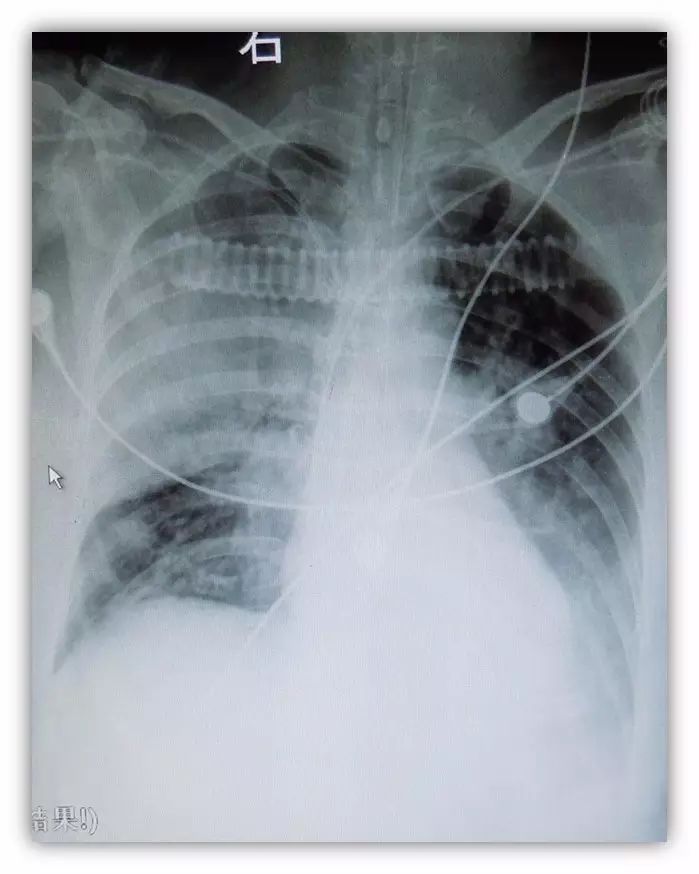

无心律失常发作,但持续高热40.5°,点头样呼吸,饱和度低,无尿

SIMV,PC/PEEP20/10cmH2O, F16次/分,FiO2:100%, T39℃,BP80/40mmHg(股动脉),P80-118bpm SPO2 85-88%, RLS8级,双瞳等大同圆,双无干湿罗音,无哮鸣音,心率80-118次/分。腹-,四肢无自主活动,四肢指端肿胀明显。

多巴胺20ug/kg/min

去甲肾上腺素1.5ug/kg/min

APACHE II 41,死亡率82%